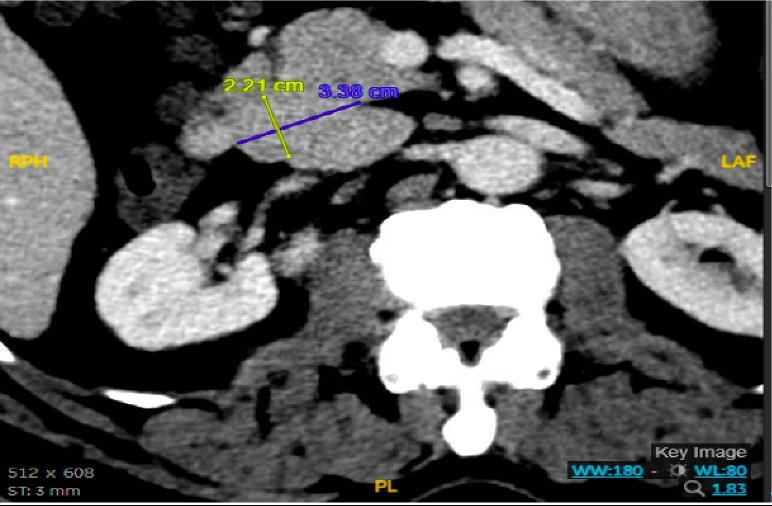

He underwent a CT-abdomen/pelvis with intravenous contrast in the emergency department which revealed an enhancing 3.4 cm mass in the head of the pancreas with retroperitoneal lymphadenopathy. MRI of the abdomen confirmed the presence of a 3.2 cm enhancing pancreatic head mass with direct extension into the second portion of the duodenum and multiple enlarged retroperitoneal lymph nodes. EGD was remarkable for edema and granularity in the first portion of the duodenum. Endoscopic ultrasound (EUS) was notable for a hypoechoic and heterogeneous irregular mass in the pancreatic head measuring 25 mm by 23 mm in maximal crosssectional diameter with invasion into the serosa and muscularis mucosa of the duodenum. Fine needle aspiration of the pancreatic mass for cytology revealed a well-differentiated pancreatic neuroendocrine tumor (Ki-67 index <1%). Gastrin levels were ordered. He presented again to the hospital 3 weeks later with worsening epigastric abdominal pain and nausea despite adhering to PPI therapy. CT-abdomen revealed new proximal duodenal ulcerations. Gastrin level from the prior admission was noted to be 1988 pg/mL. He subsequently underwent a Whipple's procedure with no complications and was discharged home with a planned EGD surveillance in 6 months.

Figure 1: CT Abdomen and Pelvis with contrast showing a suspicious mass in the second portion of the duodenum/pancreatic head.